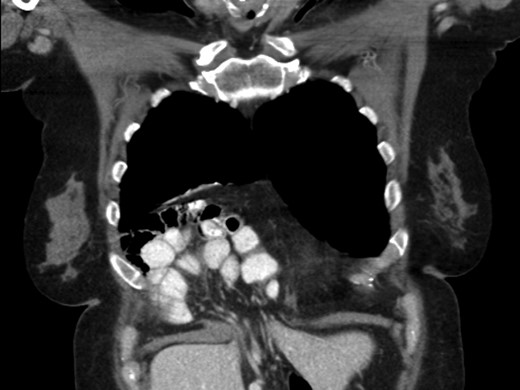

A 69-year-old female was referred to our clinic for an incidental finding of a large Morgagni hernia found on a recent CT chest scan for lung cancer screening. Patient reported occasional shortness of breath after prolonged ambulation but denied chest pain. She did have remote history of acid reflux symptoms but nothing recently. She denied issues with prematurity or issues with development as an infant, chest trauma, or MVA history. She did complain of occasional right shoulder pain but attributed this to arthritis. Denied history of heart attack, stroke, DVT, or PE. She had a 30-pack-year smoking history but quit a year prior. She was up-to-date on her colonoscopy, current within the past year. She denied hematochezia and melena, bowel habit changes or major body weight changes as well as any current abdominal pain. On examination her vitals were within normal parameters. Heart and lungs were unremarkable. Abdominal examination was soft with normal bowel sounds and nontender. Remainder of examination was unremarkable. Laboratory values included a normal CBC and BMP. A CT chest scan had demonstrated a large retroxyphoid hernia of Morgagni involving several loops of small bowel and transverse colon located in the right inferior hemithorax (Figs 1 and 2). No evidence of acute incarceration or strangulation were noted. A detailed discussion was undertaken with the patient regarding her hernia and she was consented for a laparoscopic repair with mesh.

Another slice of the CT scan of the chest revealing the large size of this Morgagni hernia with multiple loops of small bowel and colon in the right inferior hemithorax.